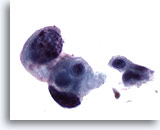

Figure 31Catheterized urine, high grade urothelial carcinoma

High grade urothelial carcinomas often are abundantly cellular. 20x

High grade urothelial carcinomas often are abundantly cellular. 20x

Figure 31

Catheterized urine, high grade urothelial carcinoma

High grade urothelial carcinomas often are abundantly cellular.

20x

Catheterized urine, high grade urothelial carcinoma

High grade urothelial carcinomas often are abundantly cellular.

20x